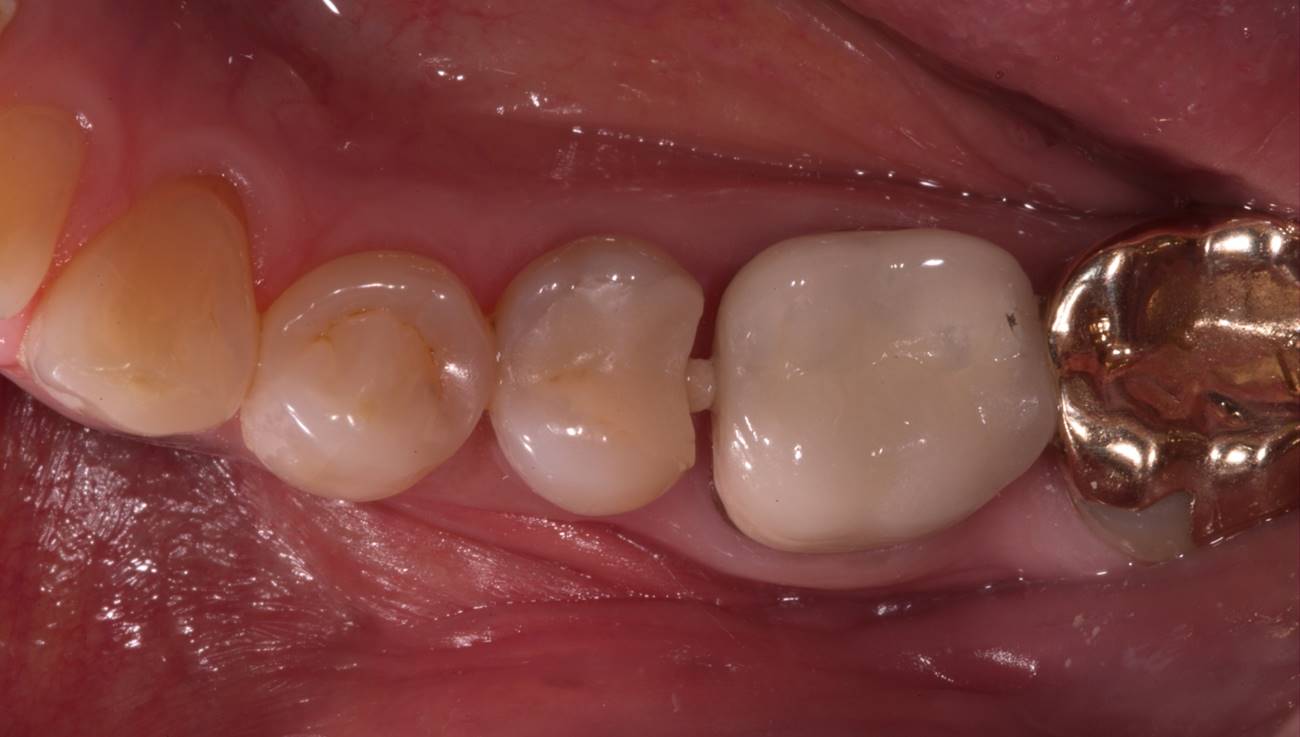

Fig 5. Preoperative view of a patient who presented with two defective amalgam restorations requiring replacement.

Figure 5